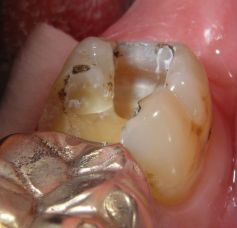

Warum ist das wichtig? Nun, Amalgam ist nicht gleich Amalgam. Es gibt, wie auch bei Composites, gravierende Qualitätsunterschiede schon im Material, die voll auf die Haltbarkeit der Füllungen durchschlagen. In einer Meta-Analyse haben sich Gamma-2-freie Amalgame mit Zink als besonders haltbar gezeigt - nach 13 Jahren waren noch 85 von 100 Füllungen im Mund. "Epoque 70" ist solch ein Amalgam und enthält darüberhinaus 70% Silber im Metallpulver. Dadurch bleibt es auch langfristig silbrig-hell, die Füllungen werden nicht schwarz. Die Bilder sind anklickbar! | ||||||||||||||||||||||||||||||||||||||||||||||||||||||||||||||||||||||||

![]() | Die Füllungen links wären auch in Composite gut vertretbar gewesen, die Füllungen rechts halten in Amalgam sicher länger als in Composite. Diese Amalgamfüllungen sind alle im Oberkiefer und im Alltag nicht sichtbar. |